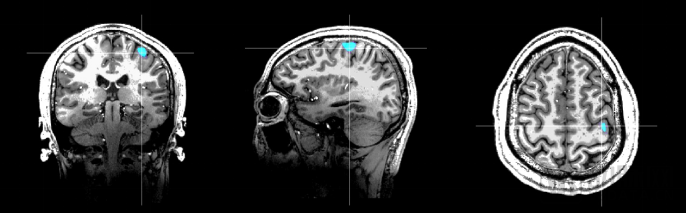

Marvel MEG®脑磁图仪健康人右手运动功能区与7.0T核磁影像融合结果

Marvel MEG®脑磁图仪基于未磁科技完全自主知识产权的量子精密磁场测量技术-原子磁力计,组成高达128通道的高密度脑磁探测阵列且无串扰,灵敏度达到了10fT(1fT=10-15Tesla)量级,以非侵入方式检测和显示大脑神经组织放电活动产生的磁场信号,进行脑功能成像。由于兼备高时间分辨率和高空间分辨率,同时具有无创、无辐射、无需造影剂的特点,因此Marvel MEG®脑磁图仪是理想的脑功能成像技术,可为癫痫诊断与病灶定位、脑功能区定位及评估、神经调控靶点定位与效果评估、认知障碍评估、精神障碍评估、脑发育评估等临床及科研领域提供全新手段。